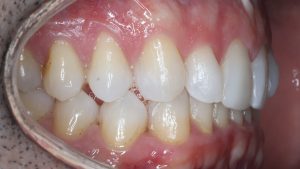

Maloclusión clase II

Se caracteriza por una relación anormal entre los dientes superiores e inferiores, donde los dientes superiores están demasiado adelantados en comparación con los inferiores.

Esto puede generar problemas funcionales, como dificultad para masticar, y también afectar la estética facial.